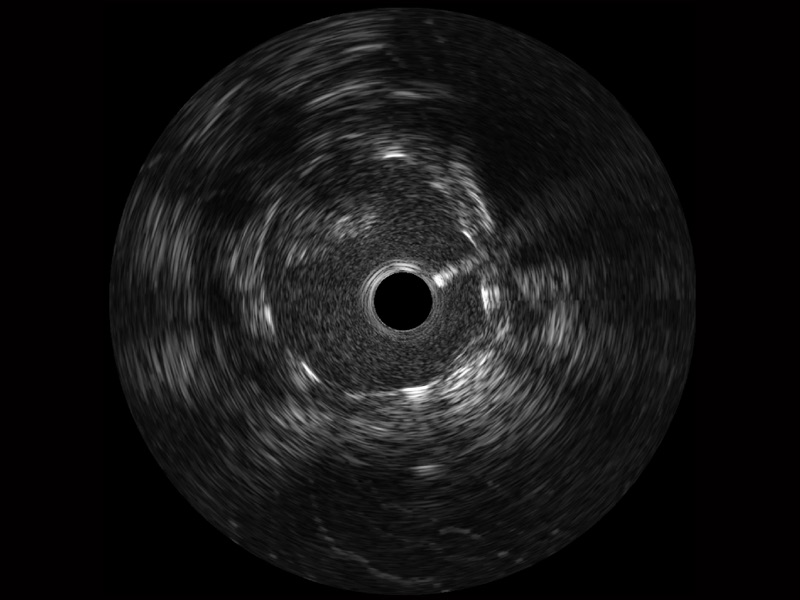

银河优越会宽频IVUS图像

传统IVUS图像

对比传统IVUS导管成像,银河优越会宽频IVUS图像的近场支架梁显影更细腻,远场中膜外血管仍清晰可辨,兼顾远中近,兼顾分辨力与穿透深度